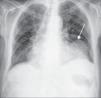

Apresentava no ECG sinais de EAM prévio (fig. 2) e no Rx de tórax observou-se a presença de uma massa adjacente à silhueta cardíaca (fig. 3). Repetiu ecocardiograma, que mostrou um volumoso aneurisma apical que se associava a imagem suspeita de pseudoaneurisma, com extensão ínfero-posterior e compressão do ventrículo direito (fig. 4).

O ECG está alterado na maioria das situações, podendo evidenciar ondas Q patológicas ou persistência de supradesnivelamento do segmento ST nas derivações referentes ao território enfartado. Por seu lado, na telerradiografia torácica, estão presentes em mais de metade dos casos cardiomegalia e/ou uma massa adjacente ao contorno da silhueta cardíaca, como ilustrado na figura 3. Contudo, estes achados, ainda que frequentes, não são específicos, não permitindo identificar o pseudoaneurisma nem tão pouco distingui-lo do verdadeiro aneurisma ventricular. Assim, as modalidades de imagem cardíaca desempenham um papel fulcral no melhor esclarecimento desta entidade.